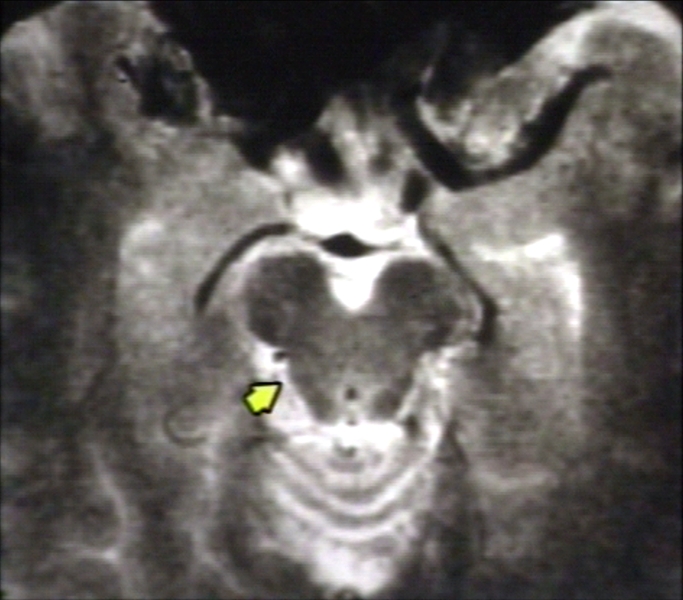

RADIOLOGY: NERVOUS: BRAIN: AMBIENT CISTERN WITH TROCHLEAR NERVE; T2 (MRI)